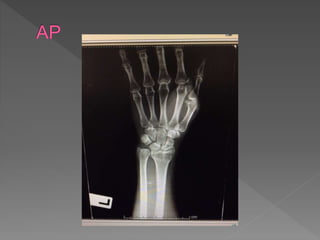

 Chiefcomplain : ปวดข้อมือซ้าย 2 ชั่วโมง PTA

› 2ชั่วโมง PTA ; ผู้ป่วยให้ประวัติว่า ขับรถมอเตอร์ไซด์ตก

หลุมแอ่งน้า เอามือซ้ายลง ขณะขับใส่หมวกกันน๊อค

ศีรษะไม่กระแทก ไม่สลบ จาเหตุการณ์ได้ตลอด หลังเกิด

เหตุปวดบริเวณข้อมือซ้าย Pain score 7/10 ข้อมือซ้าย

ผิดรูป บวม ขยับข้อมือได้ลาบาก ไม่มีอาการชา จึงส่งมา

รักษาที่รพ.มหาราช

o Leftforearmand wrist deformity

oLimit ROM of wrist joint

 Intra-articular fracture